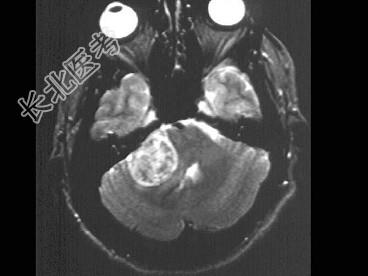

- 单项选择题男,44岁, 右耳听力进行性减弱,结合图像, 最可能的诊断为 ( )

A、听神经纤维瘤

B、三叉神经鞘瘤

C、前庭神经鞘瘤

D、胆脂瘤

E、脑膜瘤